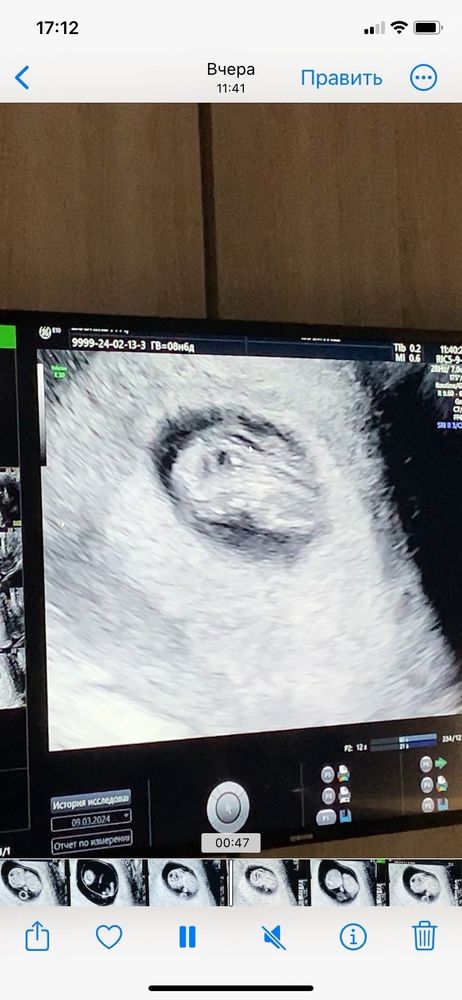

Узи 9 недель

Алина, Тогда вам только ждать скрининг или переделать УЗИ в другом месте, я на УЗИ просила измерить твп до скрининга без проблем сказали.

Юлия, на какой недельке измеряли? У меня сейчас 9.5, думаю может сегодня тогда записаться в другое место, посмотреть, что там скажут

Алина, Да на таком же сроке примерно, я каждую неделю ходила на УЗИ др скрининга